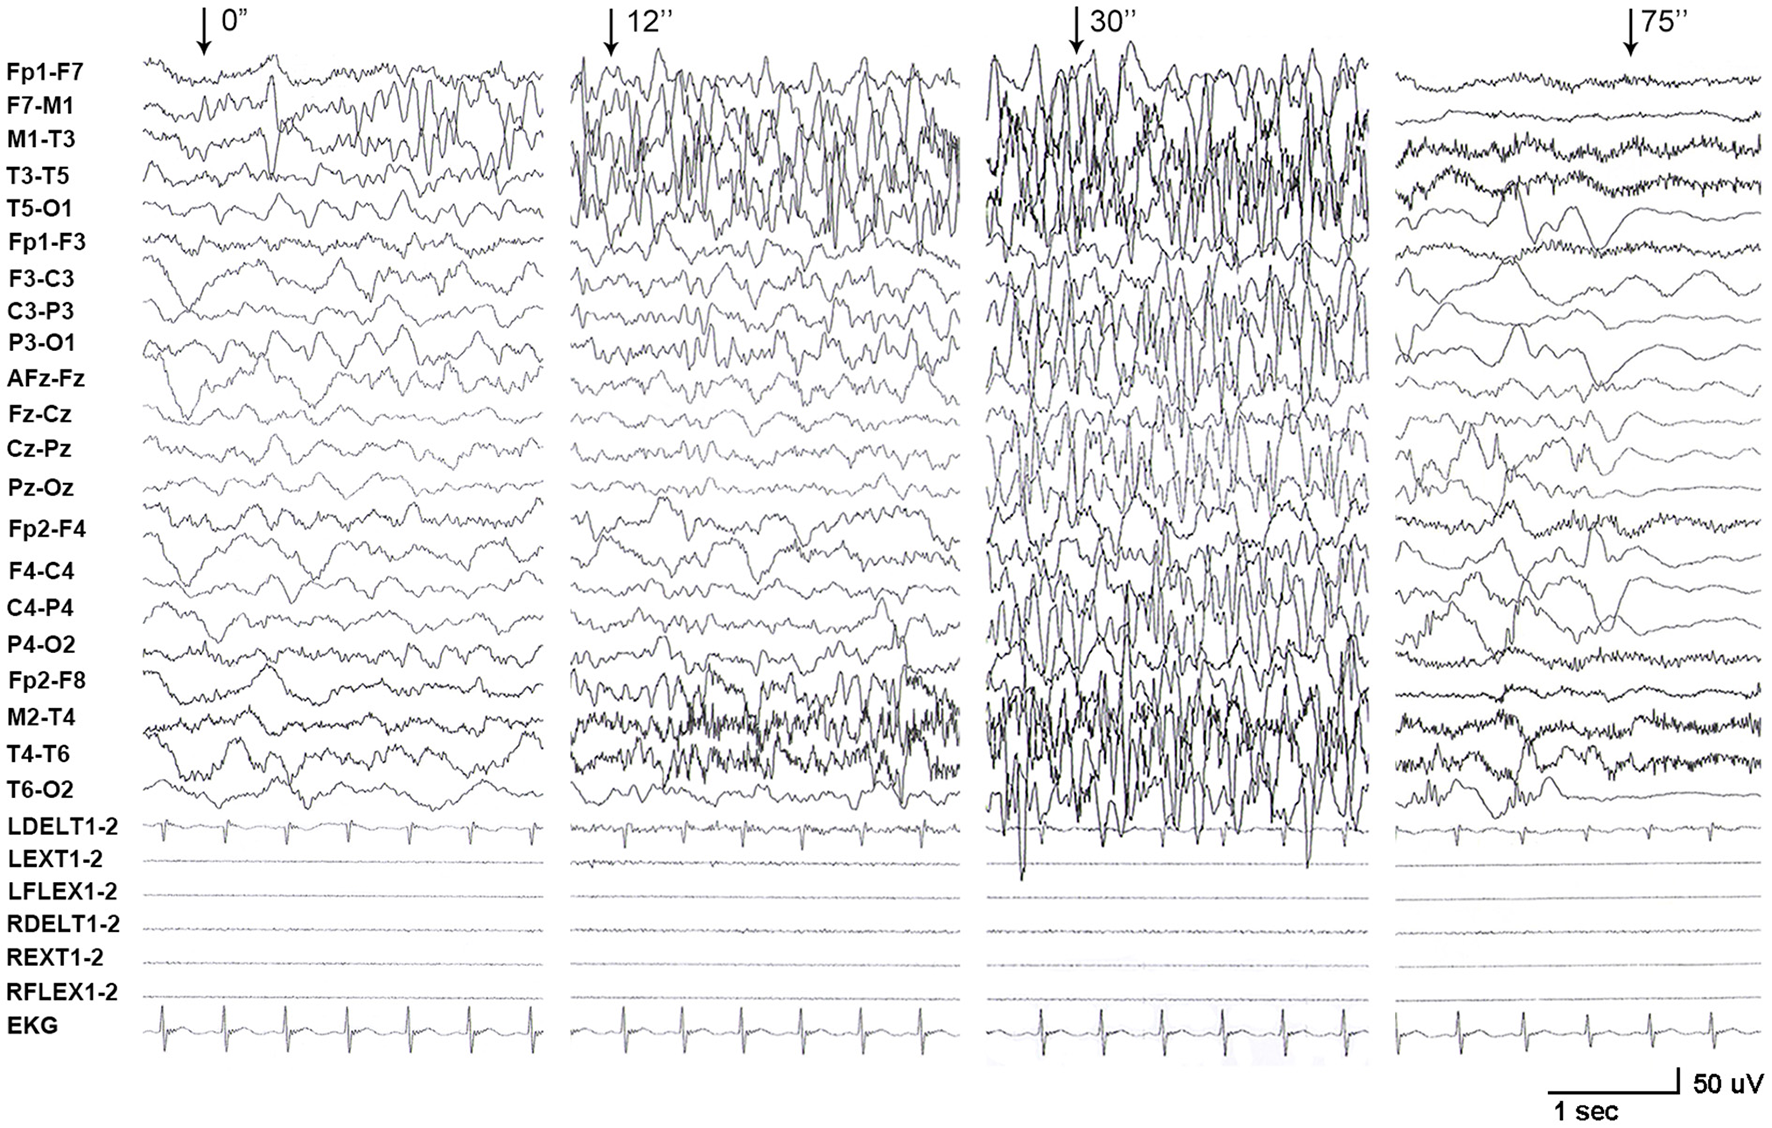

One de novo PRRT2 mutation was identified in a child with infant seizures. The child was a full-term boy who was born to healthy non-consanguineous parents. His early development was normal. The seizures began at the age of 4 months when breastfeeding was switched to formula feeding. He presented his first convulsion when he started sucking eagerly and vigorously. The seizure began with a deviation of head and eyes to the right, then cyanosis, and followed by the loss of consciousness and generalized hypertonic lasting about 1 min. The attacks repeated 2–10 times per day and mostly occurred during vigorous sucking. The ictal EEGs recorded a seizure that started with spikes from the left frontal lobe and gradually generalized, lasting for 75 s, followed by electrical suppression (Figure 1). Interictal EEGs revealed low voltage spikes and waves in the left frontal lobe with a normal background. Brain MRI was normal. Blood routine and biochemical tests were normal. Valproate (16 mg/kg/d) was applied on the third day after onset but did not stop the seizures. Vigorous sucking was subsequently avoided by shortening interval time, extending the duration of feeding, and adding the rice paste. The child was seizure-free since then (followed-up for 2 years until now). EEG became normal in the third month after being seizure-free. Valproate was discontinued after a year. The neurodevelopment was normal at 3 years of follow-up. Using the gene panel, we failed to find any pathogenic point mutations in this child. Heterozygous PRRT2 gene deletion was identified by the computational method of CNVs (Figure 2A) and validated by the qPCR method (Figure 2B). The mutation was a heterozygous whole deletion of one allele of the PRRT2 gene, which led to haploinsufficiency. Co-segregation analysis showed that the mutation was a de novo mutation (Figure 2C).

Figure 1

EEG recordings from patient with PRRT2 variants. A long-term video electroencephalogram recorded a seizure that started with spikes originating from the left frontal lobe and gradually generalized, lasting for 75 s, followed by electrical suppression.